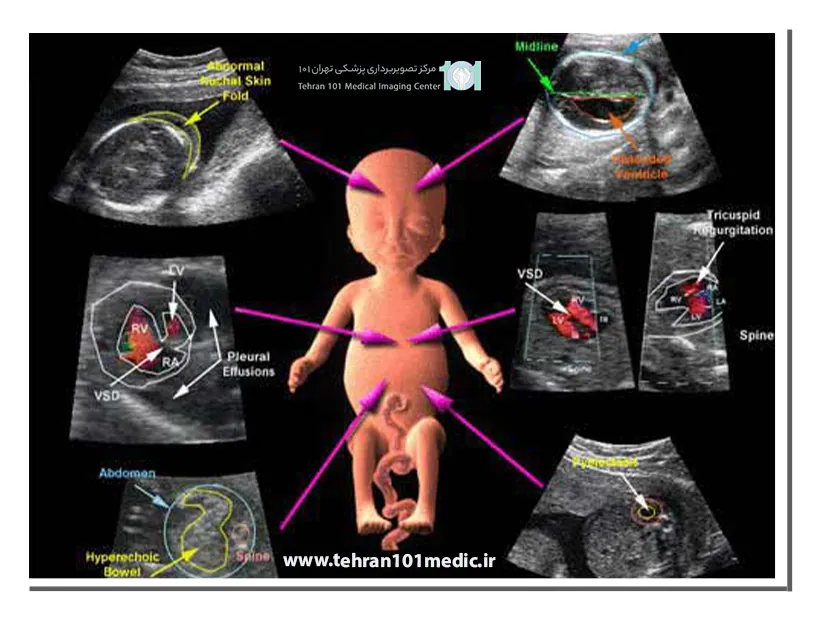

سونوگرافی داپلر چیست؟ تشخیص اختلالات قلبی و جریان خون جنین

سونوگرافی داپلر کاردیوتوگرافی

سونوگرافی داپلرکاردیوتوگرافی برای ارزیابی جریان خون در قلب جنین تجویز می شود. این روش می تواند برای ارزیابی عملکرد قلب جنین، تشخیص بیماری های قلبی و ارزیابی اثرات داروها یا درمان های خاص بر قلب جنین استفاده شود.

سلامت قلب و مغز جنین: سونوگرافی داپلر می تواند برای بررسی جریان خون در قلب و مغز جنین استفاده شود. این امر می تواند برای تشخیص مشکلات احتمالی مانند ناهنجاری های قلبی یا اختلالات مغزی استفاده شود.

سونوگرافی داپلر در دوران بارداری کمک شایانی به پزشک برای تشخیص اختلالات قلبی و جریان خون جنین می کند.